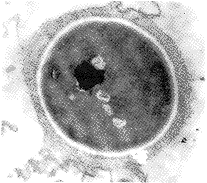

2.新隐的荚膜、粘附率及CSH的超微形态变化及抗真菌药作用后的恢复性生长:正常无药剂 作用的新隐细胞形态如图1,它能牢固粘附于vero细胞表面(图2)。使荚膜丧失的氨苄青霉素 (图3)、二性霉素B及氟康唑均有高低不一的CSH和粘附率变化,仅二性霉素B使CSH和粘附率 均降低(见附表)。氨苄青霉素和二性霉素B可使胞壁外层光亮反应(图4),二药均使CSH呈 低值,氟康唑增高CSH,无上述壁外层特征性改变。雌二醇、地塞米松及甲氨蝶呤均降低CSH 和粘附率,伴有类似氨苄青霉素所致的胞壁外层光亮区改变(图3、4),并对荚膜的影响甚 小或无。可见荚膜与CSH和粘附性变化的关系不明显,三者的致病关系也不清楚。抗真菌药 二性霉素B和氟康唑作用新隐后的恢复性生长及伴随的CSH变化表现在:随着生长菌量的增多 和CSH恢复至正常水平,其相应形态变化也会得到恢复,并有荚膜形态再生(图5)。说明CS H、胞壁形态变化及荚膜改变都是可逆的。

图1 新生隐球菌胞壁正常形态